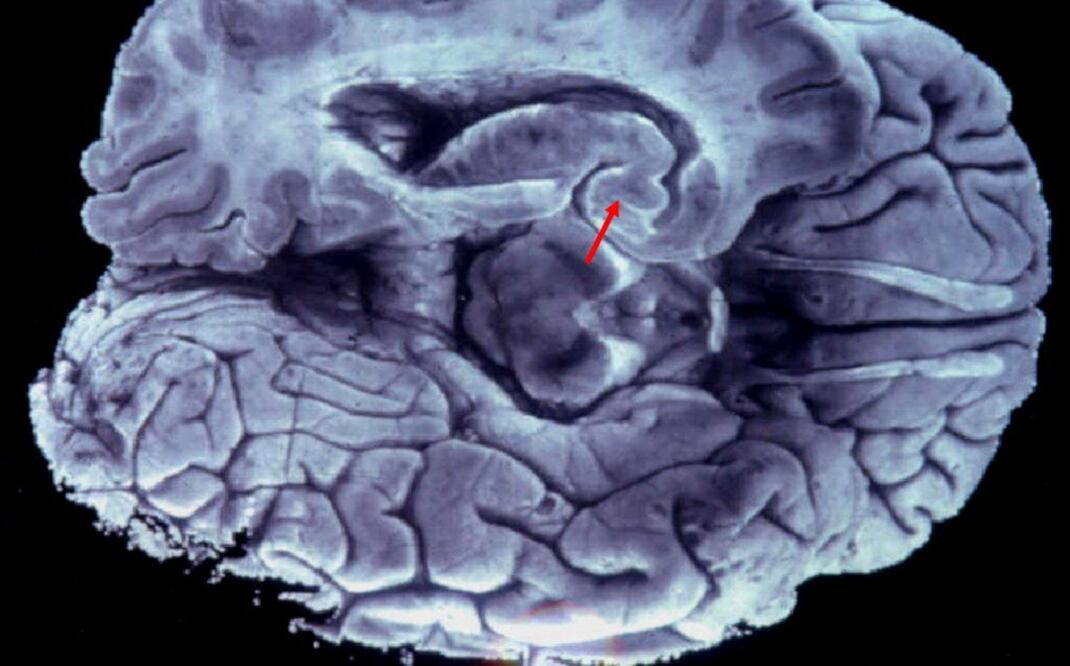

La amígdala es una de las partes más profundas del cerebro, que, desde el punto de vista evolutivo cuenta con estructuras subcorticales antiguas, como, además de la amígdala, el hipocampo, y otras posteriores como la corteza, la parte externa que cubre los dos hemisferios.

Sin embargo, dado que la amígdala es una estructura muy profunda del cerebro, estas técnicas carecen de la resolución suficiente para ver cómo funciona el proceso. Hacen falta otras técnicas, como el uso de electrodos implantados en esta región cerebral.

Este atajo es un circuito neuronal formado por células del tipo "magnocelular", las más rápidas llevando información al cerebro, incluso aunque sean de baja frecuencia, mala calidad o borrosas, explicó Strange.